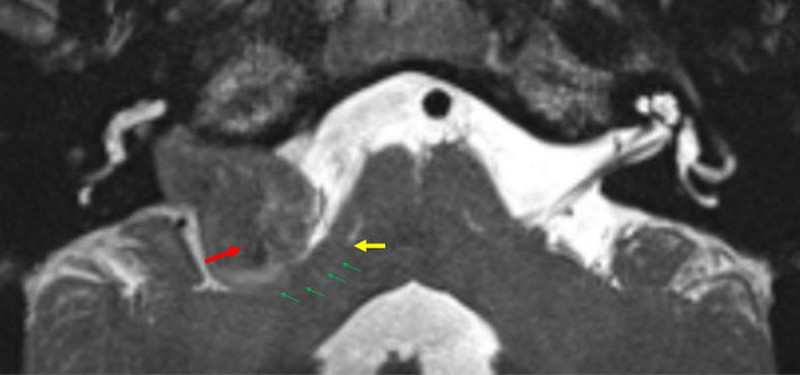

OBEN: MRT mit Akustikusneurinom, Mitte: Sicht durch das OP-Mikroskop, Unten: Billdschirm des Neuromonitoring

Das bildgebende Verfahren der ersten Wahl ist beim Schwannom die Kernspintomografie (auch Magnetresonanztomografie oder MRT), da dieses Verfahren den größten Weichteilkontrast besitzt. Ergänzend werden meist eine Computertomographie (CT), sowie Hör- und Gleichgewichtsuntersuchungen durchgeführt.